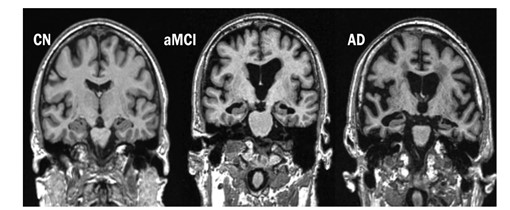

MRI images of Dementia cases in Figure 3, 4. AD leads to hippocampal atrophy and ventricular enlargement, healthy brain and brain images with AD are given in Figure 5 in an elderly, cognitively normal (CN) individual, an individual with amnestic mild cognitive impairment (aMCI) and an individual with Alzheimer's disease (AD) by obtaining images from the relevant literature.

Figure 5: Progressive atrophy (medial temporal lobes) in an elderly, cognitively normal (CN) individual, an individual with amnestic mild cognitive impairment (aMCI), and an individual with Alzheimer's disease (AD) [61].